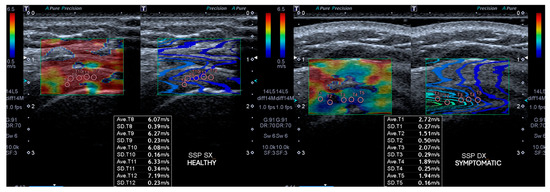

2.2.1. Outcomes Ultrasound Evaluation

2.2.2. Ultrasound Evaluation

| SWEv affected side T0 | 3 ± 0.7 |

| SWEv affected side T1 | 5.7 ± 1.8 |

| SWEv healthy side T0 | 6.9 ± 1 |

| SWEv (m/s) | 3.1 ± 0.7 | 5.7 ± 1.8 | 3.2 to 2.1 | 6.9 ± 1 | <0.05 |